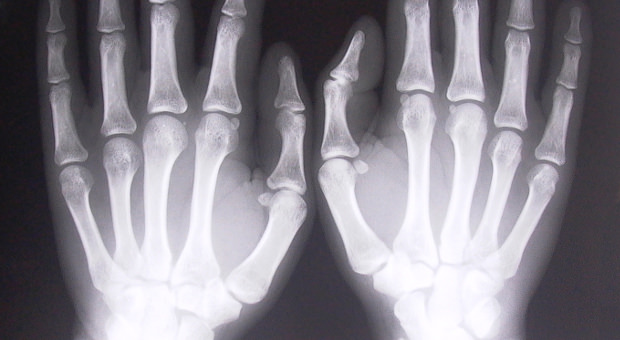

There are two general types of bone material: cortical bone, which is the dense, hard, outer shell of most bones; and trabecular bone, which is the “spongy” form of bone found at the ends of long bones, near joints and inside vertebrae.

The study showed that mutant mice lacking the Sostdc1 gene, despite having a lower trabecular bone density, had thicker, denser, cortical bone, which healed at an accelerated rate relative to their genetically normal counterparts when fractured. Furthermore, the team was able to show that suppression of the Sostdc1 gene induces a population of stem cells to rapidly expand and invade the fracture to contribute to the repair process.